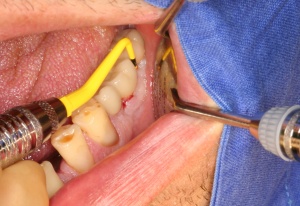

Eine weichgewebschirurgische Vorbereitung des zukünftigen Implantatlagers bereits zu diesem Zeitpunkt ist häufig ratsam. Dazu gehört unter anderem wie in diesem Bildbeispiel die Verbreiterung der Zone keratinisierter Gingiva. Eine gedeckte Einheilung des Implantates wird somit wahrscheinlicher. Therapeutisch kompliziertere Eingriffe nach der Freilegung oder sogar erst nach prothetischer Versorgung werden vermieden (Abb. 5a/b).